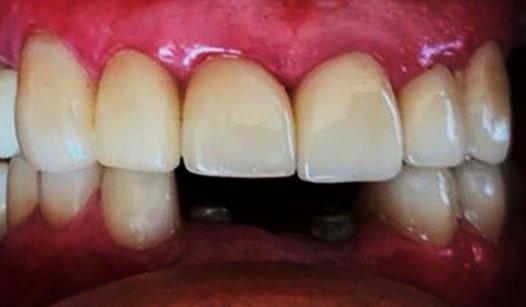

El tratamiento concluyó en 2 años y 6 meses, logrando el perfil facial deseado, con clase I esquelética, clase I canina y molar bilaterales, corrección del apiñamiento maxilar y mandibular, líneas medias coincidentes, overjet y overbite adecuados, así como la realización de la genioplastia e implantes en la zona malar. En los

estudios radiográficos finales, en la lateral de cráneo, se observa la diferencia tras 2 años de iniciado el tratamiento (Figura 8), además de la radiografía panorámica final. Debido a la forma del perfil, y con el fin de alcanzar la estética deseada, se realizó la cirugía.

En los estudios finales en las fotografías intraorales (Figura 9) se ve la línea media coincidente, el overjet y el overbite. La alineación y forma de las arcadas superior e inferior, con el

retenedor fijo de premolar a premolar (Figura 10).